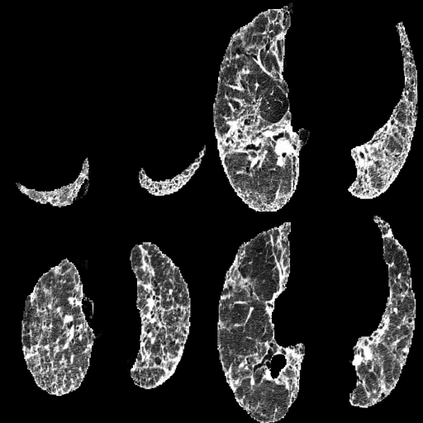

In the field of medical imaging, particularly in tasks related to early disease detection and prognosis, understanding the reasoning behind AI model predictions is imperative for assessing their reliability. Conventional explanation methods encounter challenges in identifying decisive features in medical image classifications, especially when discriminative features are subtle or not immediately evident. To address this limitation, we propose an agent model capable of generating counterfactual images that prompt different decisions when plugged into a black box model. By employing this agent model, we can uncover influential image patterns that impact the black model's final predictions. Through our methodology, we efficiently identify features that influence decisions of the deep black box. We validated our approach in the rigorous domain of medical prognosis tasks, showcasing its efficacy and potential to enhance the reliability of deep learning models in medical image classification compared to existing interpretation methods. The code will be publicly available at https://github.com/ayanglab/DiffExplainer.